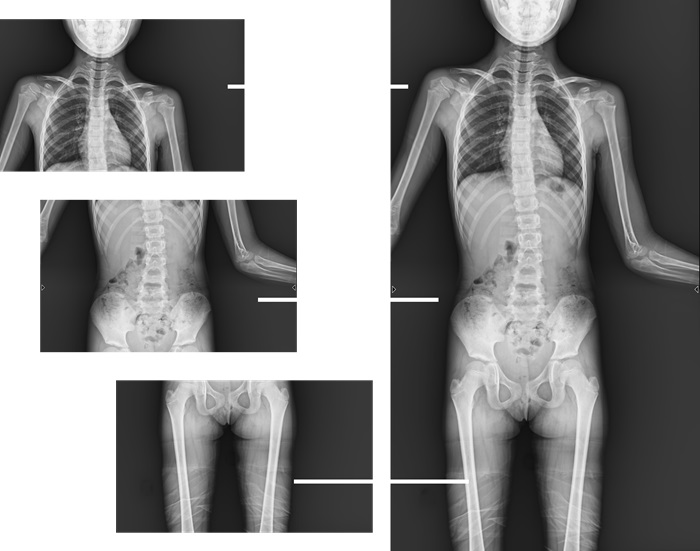

而且,影像采集幅面大,17×17英寸超大視野可覆蓋成年人的全胸全腹,并且能在連續(xù)動態(tài)中實時高清點片,從而達到精準診斷的目的。設備靈活高效的多維度運動設計,也帶來了更加智能化、人性化操作體驗,可大幅提升檢查效率。

與此同時,普利德動態(tài)平板DRF還具有全身拼接功能,尤其適用于全脊柱和全下肢攝影,為臨床提供高精度圖像,輔助脊柱畸形矯形治療、康復檢查。